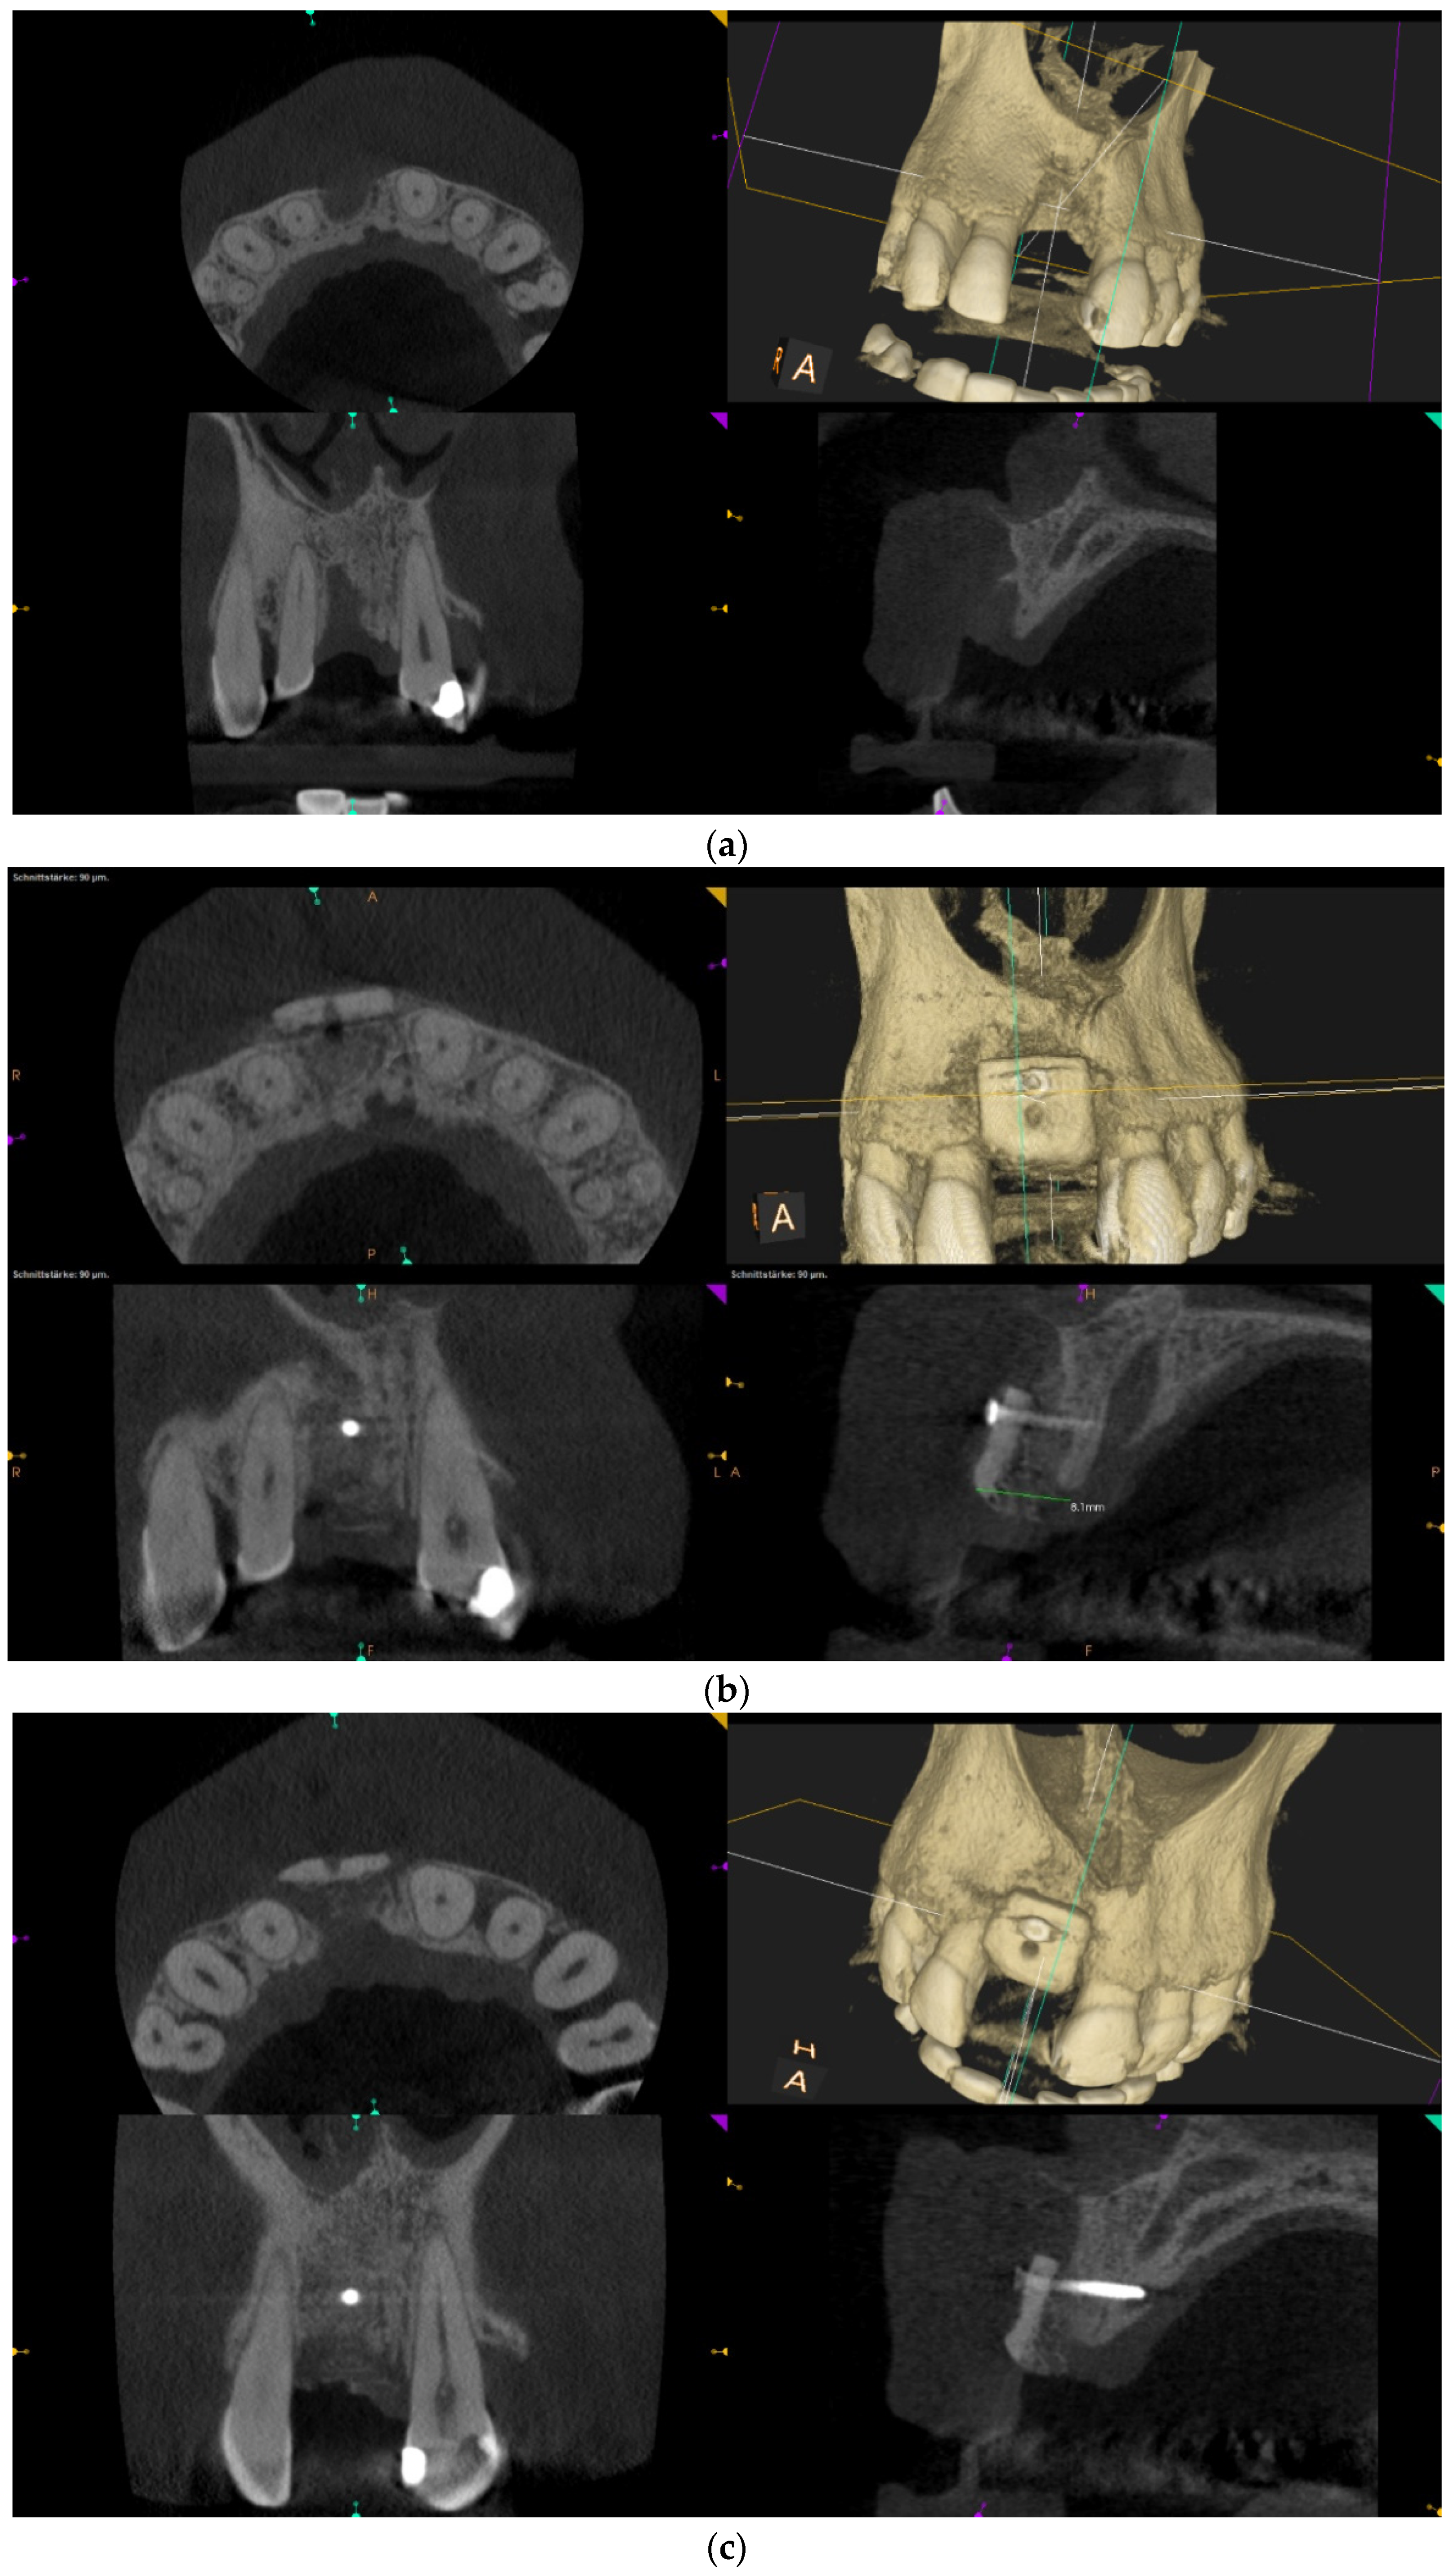

Over-contouring was defined as an over-augmentation of the alveolar process beyond the extent of the adjacent bone level (Figure 1). The reason for over-augmenting the alveolar process is often an anticipated shrinkage of the bone substitution material during the healing phase. Two patients were selected as examples to illustrate the term “over-contouring”. Patient 1 showed a Class III defect in the maxilla, and the alveolar ridge augmentation performed for correction was over-contoured (Figure 2). Patient 2 also showed a Class III defect in the maxilla, but the alveolar ridge augmentation performed for correction remained at the level of the surrounding bone (Figure 3).

Figure 2.

Clinical example of over-contouring. (a) Class III defect with pronounced vestibular deficit and minor vertical deficit. (b) Post-OP: Attachment of a cortico-cancellous allogeneic bone block. Vestibular over-contouring with the cortical plate and vertical over-contouring of the block can be seen. The block protrudes over the limbus alveolaris, i.e., over the bone border of the adjacent teeth. (c) After 5 months: the over-contoured portion of the cortical portion of the block was not resorbed, but part of the cancellous portion of the block was palatally resorbed away. (d) The over-contoured block penetrates the mucosa. The cortical portion is revealed.